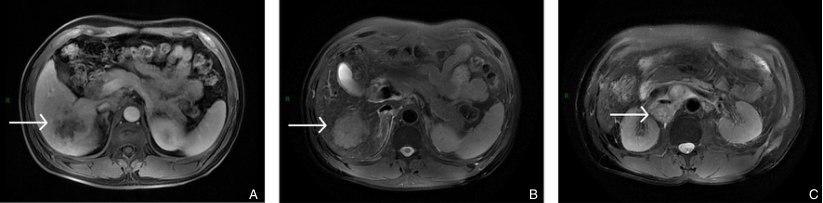

图2 患者转化治疗前MRI A-B:病变在T1加权成像(T1WI)中呈稍低信号,在T2加权成像(T2WI)中呈高信号;C:肿大淋巴结Fig.2